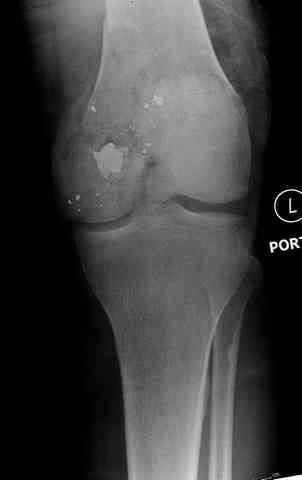

Здесь представлены несколько случаев лечения огнестрельного перелома

2 внутрисуставной перелом дистального бедра с удалением пули

Условием для обязательного удаления пули считаем ее внутрисуставное расположение из-за возможного сатурнизма, или когда во время операции она без труда удаляется, а также поверхностно расположена.